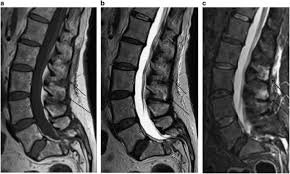

Signs and symptoms include low back pain, pain that radiates down the leg, numbness around the anus, and loss of bowel or bladder control. Anatomy of lower lumbar and sacral spine (lavy 2009). Mri of marked dural sac compression by surgical in the immediately postoperative period after uncomplicated lumbar laminectomy.// lumbar cauda equina syndrome associated with the use of gelfoam: Cauda equina syndrome (ces) is a condition that occurs when the bundle of nerves below the end of the spinal cord known as the cauda equina is damaged. The spinal cord ends at the lower level of t12 or l1 vertebrae. Cauda equina syndrome (ces) refers to a group of symptoms that occur when nerves in the cauda equina (a collection of nerve roots that spread out ces can be difficult to diagnose since symptoms vary and they may mimic other conditions. Cauda equina syndrome (ces) is a particularly serious type of nerve root problem. Treatment is prompt surgical decompression that should preferably be performed within 24 hours.

Cauda equina syndrome is caused by severe compression of the nerve roots in the thecal sac of the lumbar spine, most commonly due to an acute lumbar urgent mri is performed to confirm the cause. Cauda equina syndrome (ces) is a condition that occurs when the bundle of nerves below the end of the spinal cord known as the cauda equina is damaged. Mris are valuable in diagnosing the cause of cauda equina syndrome as. Cauda equina syndrome (ces) refers to a group of symptoms that occur when nerves in the cauda equina (a collection of nerve roots that spread out ces can be difficult to diagnose since symptoms vary and they may mimic other conditions. Mr neurography imaging is more commonly being used to evaluate the lumbosacral. Learn about diagnosis, including mri testing. Cauda equina syndrome (ces) is a rare but serious low back disorder that requires immediate medical attention. Tests that may be used to diagnose ces include mri, ct. Cauda equina syndrome may result from any lesion that compresses ce nerve roots. Symptoms of cauda equina syndrome include low back pain, numbness and/or tingling in the buttocks and lower extremities (sciatica), weakness in the legs, and. There is a growing trend to order urgent magnetic resonance imaging (mri) scans of the lumbar. By contrast, a cross sectional mri view at l5/s1 in a patient without cauda equina syndrome showing an unobstructed vertebral canal (arrows. 3 treating cauda equina syndrome.

2 receiving diagnostic tests and examinations. This is a rare disorder where there is pressure on the nerves. Sagittal mri of a patient with cauda equina syndrome secondary to a large lumbar disk herniation. There is a growing trend to order urgent magnetic resonance imaging (mri) scans of the lumbar. Cauda equina syndrome (ces) occurs when there is dysfunction of multiple lumbar and sacral nerve roots of the cauda equina.

Chronic cauda equina syndrome, defined as persistent damage of the cauda equina nerve roots within the spinal canal can be a challenging diagnosis with varied presentations.